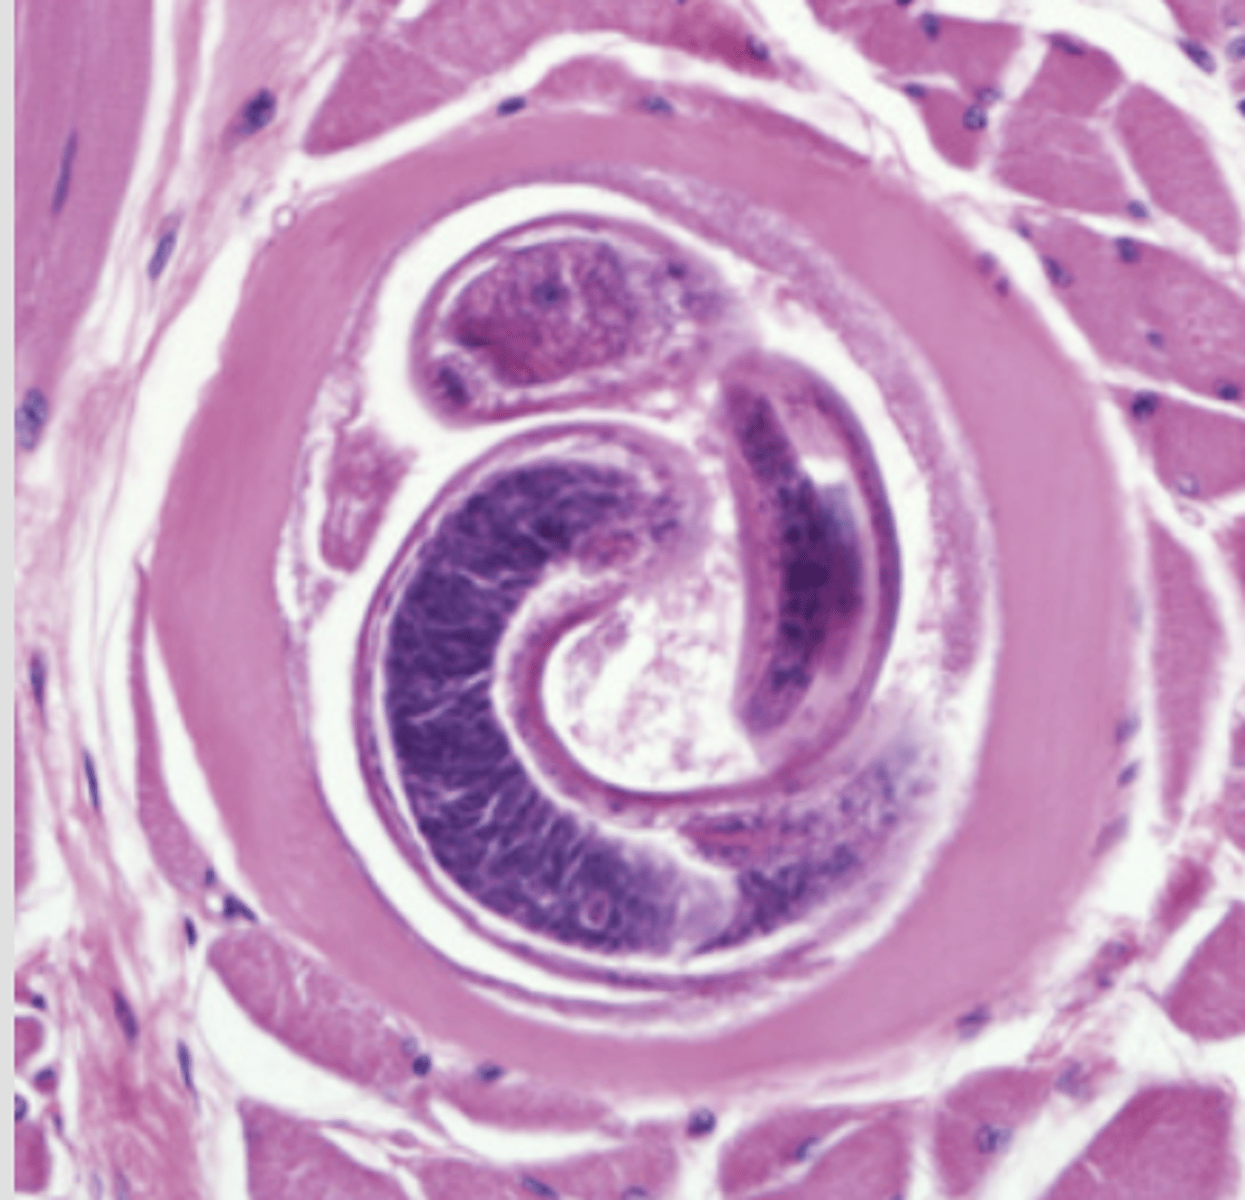

Trichinella spiralis